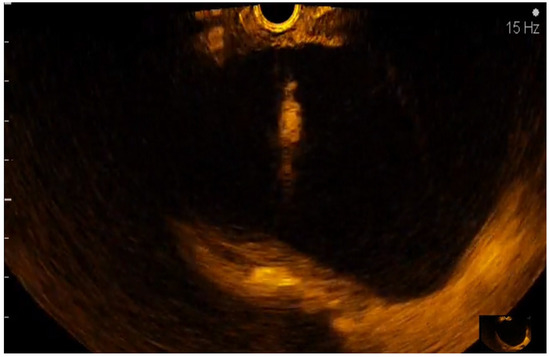

2.4. EUS Equipment and Techniques

2.5. CE-EUS Procedure